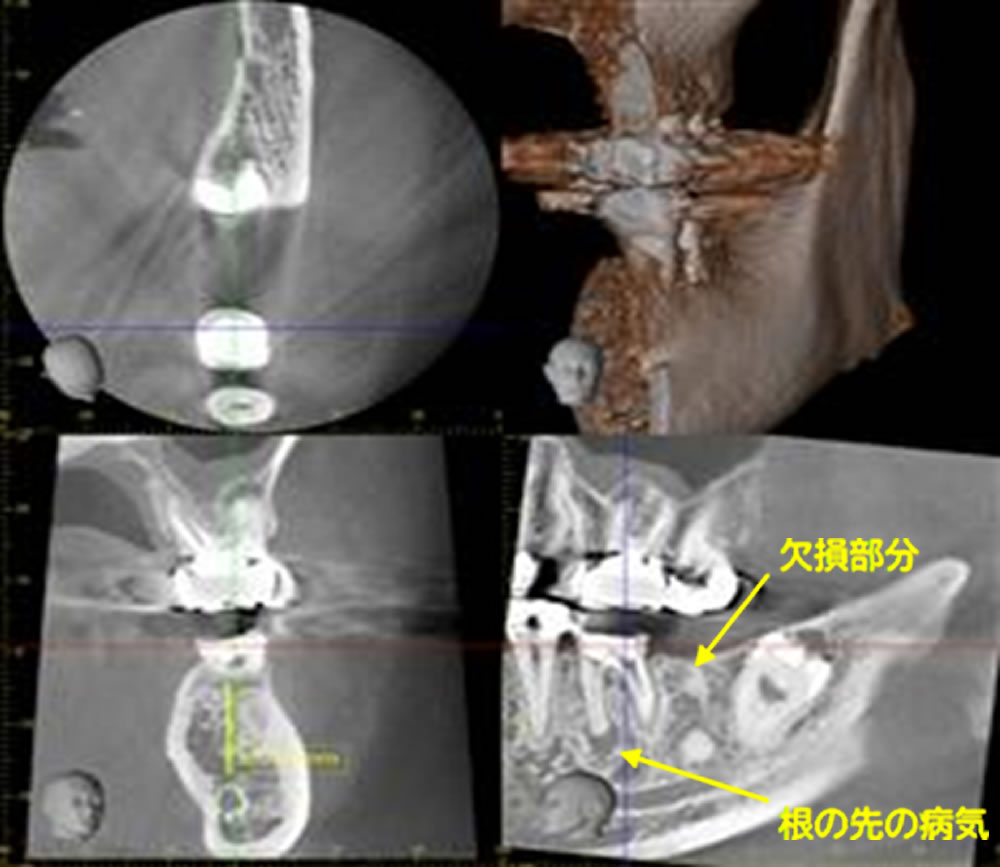

CT精密検査

CT撮影を行い、歯や骨の状態を確認します。治療をしても改善がみられず、腫れを繰り返している部分に黒い影があります。根の先にできた膿(根尖病巣)です。欠損部分の骨の高さは十分にありますが、横の厚みが若干少ないことが確認されました。骨のボリュームが足りない部分には人工骨で補填が必要です。